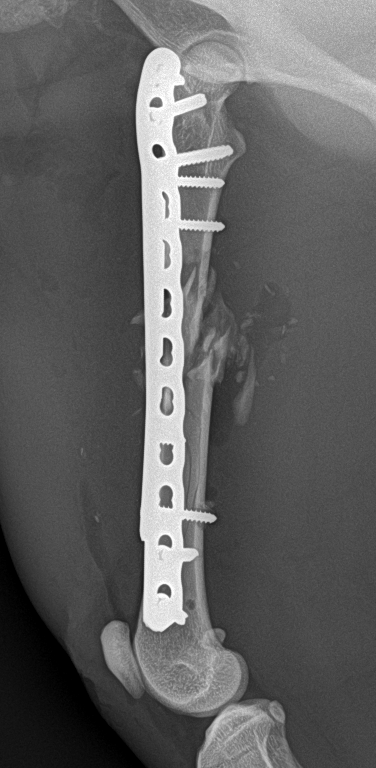

画像だと少しわかりにくいかもしれませんが、骨が癒着しぶらぶらだった状態からしっかりと固まってきております。

手術直後